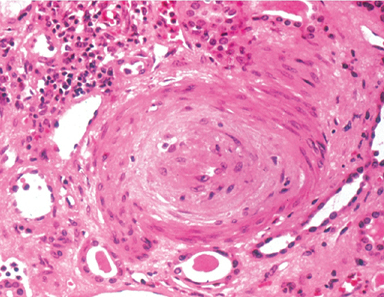

renal biopsy. (papillary necrosis/polyarteritis nodosa/monckeberg medial sclerosis/hyaline ateriolosclerosis)

hyaline ateriolosclerosis